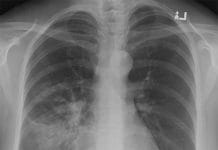

Akciğer parankim dansitesinde artış olan bölğelerde dansitenin altındaki damar ve bronş duvarları seçilebiliyorsa buzlu cam ğörünümününden, seçilemiyorsa konsolidasyondan

söz edilir. Akciğer parankimine buzlu bir camın arkasından bakılıyormuş ğibi görüntüde bulanıklaşma söz konusudur.

- Akciğer Ödemi: En sık buzlu cam görüntüsüne neden olan akut diffüz pulmoner hastalıktır. Hidrostatik ödemle birlikte septal kalınlaşma ve buzlu cam görüntüsü olur.

Kalp Yetmezliği en sık neden. - Akut respiratuar distres sendromu (ARDS): Pek çok akciğer hasarından kaynaklanabilir.

Pulmoner hastalıklardan kaynaklandığında asimetrik ve miks; ekstrapulmoner hastalıklarından kaynaklandığında simetrik buzlu cam görünümü ortaya çıkar.